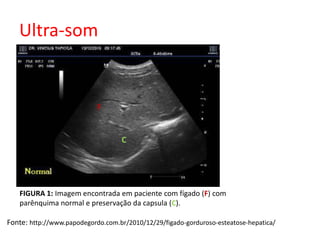

FIGURA 1: Imagem encontrada em paciente com fígado (F) com

parênquima normal e preservação da capsula (C).

Fonte: http://www.papodegordo.com.br/2010/12/29/figado-gorduroso-esteatose-hepatica/

Ultra-som C F FIGURA 1: Imagem encontrada em paciente com fígado (F) com parênquima normal e preservação da capsula (C). Fonte: http://www.papodegordo.com.br/2010/12/29/figado-gorduroso-esteatose-hepatica/